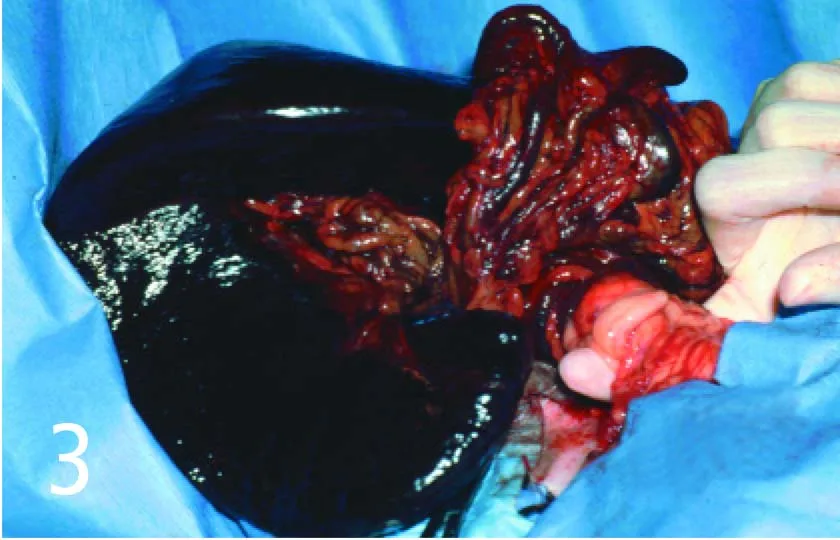

Avoid the temptation to untwist the pedicle, even though it facilitates ligation of vessels to the spleen in cases of torsion (Figure 3). It can release thrombi and vasoactive compounds into the circulation, causing significant hemodynamic disturbance. Divide the distal pedicle into several en masse ligations, or attempt to partially untwist just enough of the pedicle distal to the pancreas to help isolate the main splenic vessel divisions for ligation. Once the pedicles have been clamped and the spleen removed, completely untwist the proximal aspect to release the pancreas. If the pancreas appears compromised, perform a partial pancreatectomy.